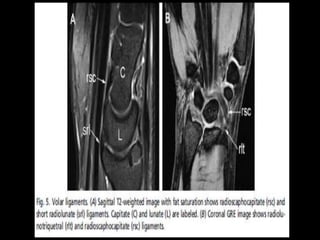

Presentation1, musculoskeletal anatomy.

• 1.

• 2.